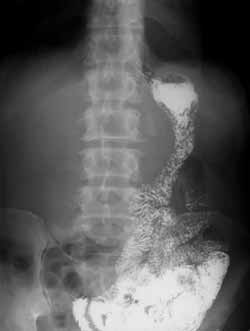

Рис. 5. Гастроэктомия с формированием эзофагоэнтероанастомоза - наиболее обширная операция, выполняемая на желудке при тотальном или субтотальном опухолевом поражении.